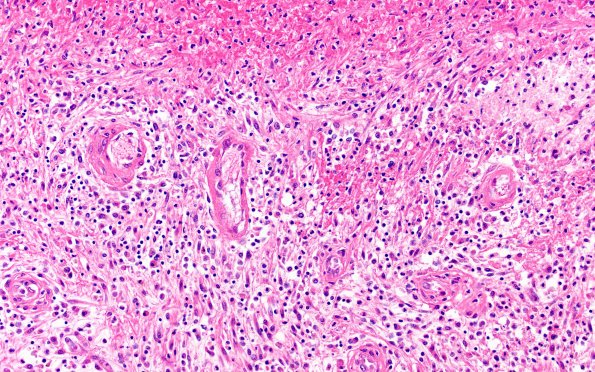

Washington University Experience | INFECTION | Bacteria | Abscess | Abscess, Subacute - Chronic | 17C6 Abscess (Case 17) N12 H&E 20X

The middle layer shows a mixed inflammatory infiltrate of lymphocytes, PMNs and a few plasma cells as well as edema and numerous fibroblasts which may look atypical with mitoses. Notice the proliferation of hyalinized blood vessels. (H&E)